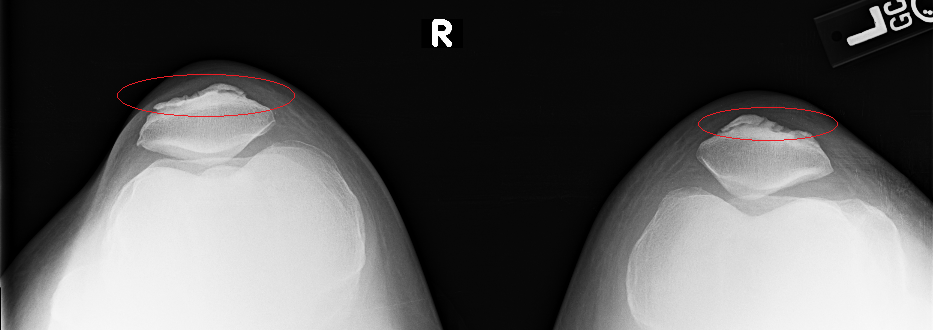

Your sunrise pateler views (bottom knee cap floating in space view) are worrying. You are developing bone avulsions (the part where it looks like it is separating) most likely due to impact injury coupled with straining tendons. You got to start wearing knee pads for what ever you are doing that is impacting them. If that continues in the same path, even walking will be a chore.

On the lateral view I can see see a section of calcification on the anterior aspect. ................... The worrying part is just bellow the calcium I see a region that looks like a chip fracture or an older one. Its the diagonal line with the offset. Of course, I could just be nitpicking and just seeing something that is an optical illusion.